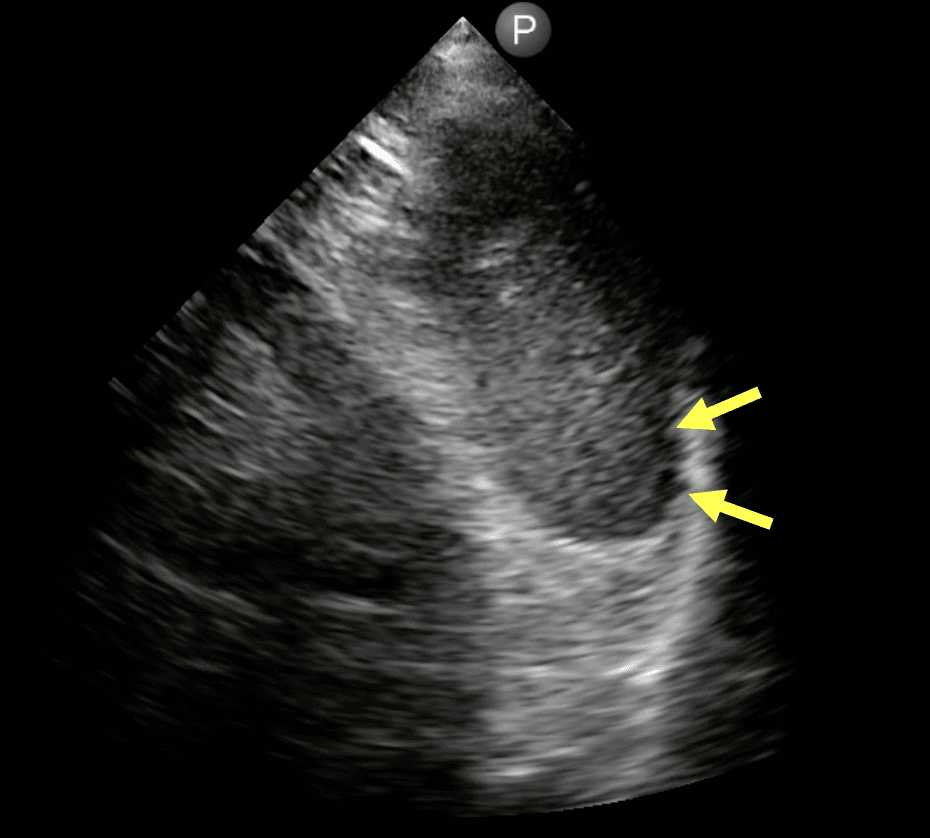

Diagnosis of Pneumoperitoneum Using POCUS

Maria Paulina Maya Jaramillo; Alejandro Cardozo Ocampo – This case report reinforces the value of integrating POCUS into the initial evaluation of acute abdominal pain, suggesting its use as an adjunct to traditional imaging methods in the emergency department.